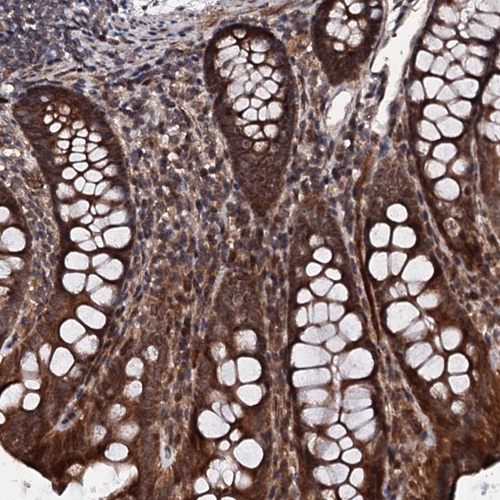

Immunohistochemical staining of human colon shows strong cytoplasmic and nuclear positivity in glandular cells.